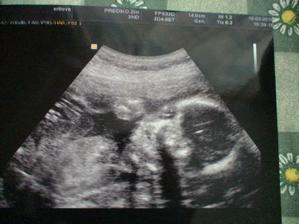

Velký utz 19.3. 19tt+6 dopadl výborně, doktorka kontrolovala všechny orgány: mozek, srdíčko-ukazovala nám srdeční tepnu a plicní žílu, bránici, ledviny, močový měchýř, ručky, nožky-i šlapky 🙂 Měřila stehenní kost - odpovídá. Měřila hlavičku- odpovídáme přesně tt. Miminko váží 300g. Placenta je uložena dobře, nebrání přir.porodu:-) Poslouchali jsme srdíčko. Za 3 týdny kontrola žaludku, teď nebyl naplněn plod. vodou.. mimíško bylo vyčurané🙂))

Utz 13.4.((23tt+3) Prediko : Prďolka odpovídá tt podle hlavičky i stehenní kosti. Žaludek už byl krásně vidět. Všechno v pořádku. Plodové vody dostatek. A čekáme DĚVČÁTKO 🙂))))) váží 600g.